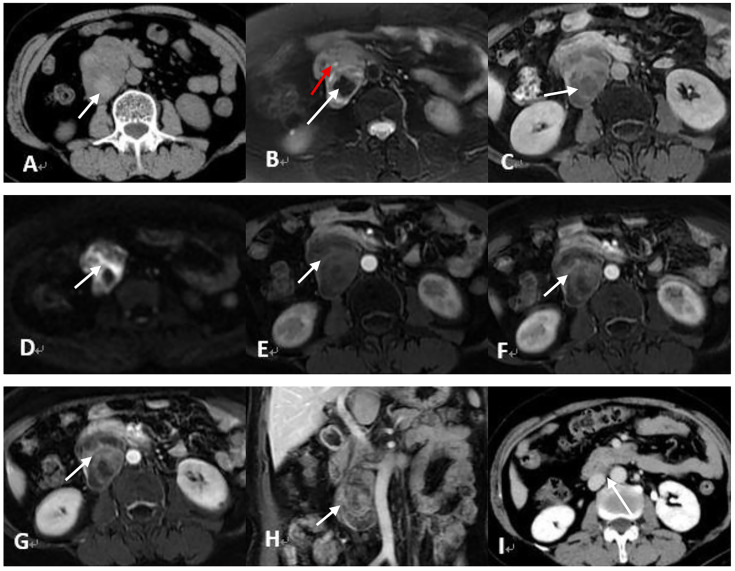

成人型卵巢颗粒细胞瘤是一种罕见的低级别恶性肿瘤,其特点是复发晚,临床表现不典型。本研究报告2例复发的成人型卵巢颗粒细胞瘤,具有不同的时间线和解剖部位,其中1例术后两次复发。我们分析其影像学特征、手术处理、组织病理学、术后随访,并复习相关文献。这些病例强调了长期随访的重要性,提高了对罕见复发部位的认识,强调了影像学的诊断价值和对成人型卵巢颗粒细胞瘤患者个性化监测策略的必要性。

Adult-type ovarian granulosa cell tumors are rare low-grade malignancies characterized by late recurrence and atypical clinical manifestations. This study reports two cases of recurrent adult-type ovarian granulosa cell tumor with distinct timelines and anatomical sites, including one case with two postoperative recurrences. We analyze their imaging features, surgical management, histopathology, postoperative follow-up, and review relevant literature. These cases highlight the importance of long-term follow-up and raise awareness of rare recurrence sites, emphasizing the diagnostic value of imaging and the need for individualized surveillance strategies in adult-type ovarian granulosa cell tumor patients.